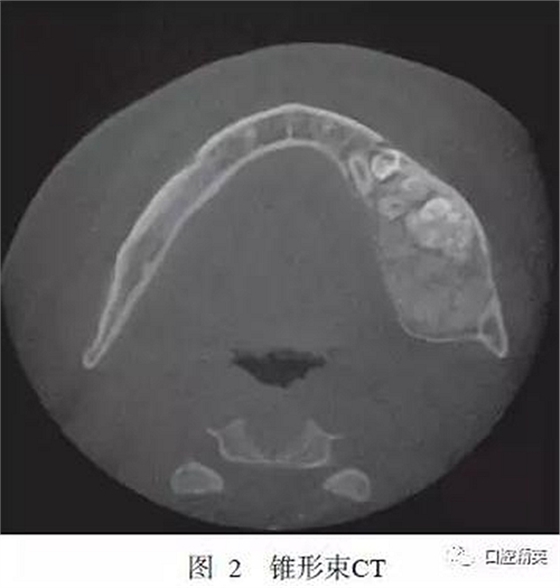

錐形束CT示:左下頜D5~D7缺失,D5~D7位置下頜骨內(nèi)可見牙瘤樣結(jié)構(gòu),左下頜骨膨隆明顯,膨隆向上至下頜骨升支乙狀切跡下方,向下至下頜骨下緣,向前至下頜骨體D5位置,向后至下頜升支中份,骨質(zhì)膨隆內(nèi)可見鈣化程度不同的阻射影(圖2)。

(1)影像學(xué)檢查。OF為境界清楚的單房性密度減低區(qū),病變中央常見不透光區(qū)。FD為病變區(qū)阻射性降低,呈磨玻璃樣改變,病變與周圍正常骨質(zhì)界限不明顯。本例影像學(xué)特征為左下頜骨局部可見異常高密度團塊影,團塊密度不均勻,可見牙樣結(jié)構(gòu),病變邊界清晰,符合OF的影像學(xué)改變。